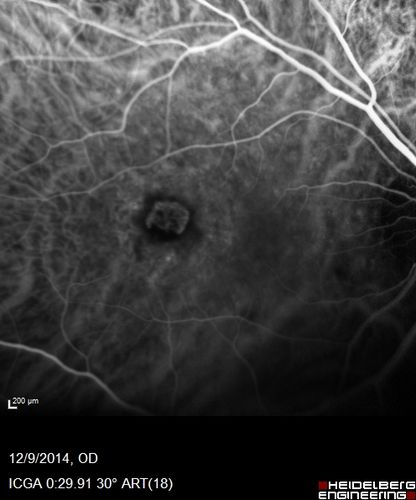

Presumed Ocular Histoplasmosis with new CNVM in right and better eye - VA 20/80 OD; 20/800 OS

Indocyanine Green Angiogram

Ocular Histoplasmosis with New CNVM in right and better eye treated with Lucentis (POHS)